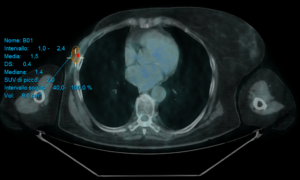

Con il paziente sdraiato supino sotto la gamma camera (il braccio abdotto nella stessa posizione che avrà durante l’intervento chirurgico), devono essere ottenute due proiezioni di acquisizione, ad esempio anteriore e anteriore-obliqua a 45° o anteriore e laterale. Per facilitare la correlazione anatomica, può essere registrata contemporaneamente una scansione di trasmissione con una fonte di cobalto-57.

La gamma camera è generalmente dotata di un collimatore a bassa energia e alta risoluzione, e le immagini planari sono acquisite (per 3–5 minuti, con una matrice minima di 128 × 128) a partire da 15 minuti dopo l’iniezione. Se necessario (in caso di drenaggio linfatico lento), ulteriori immagini possono essere eseguite a 2–3 ore (o anche fino a 16–18 ore).

In caso di mancata visualizzazione del drenaggio verso i linfonodi, può essere iniettata un’ulteriore dose (boost) del radiocolloide, si possono eseguire ulteriori massaggi del sito di iniezione e/o possono essere acquisite immagini SPECT/CT, che migliorano il rilevamento e la localizzazione del linfonodo sentinella rispetto all’imaging planare.